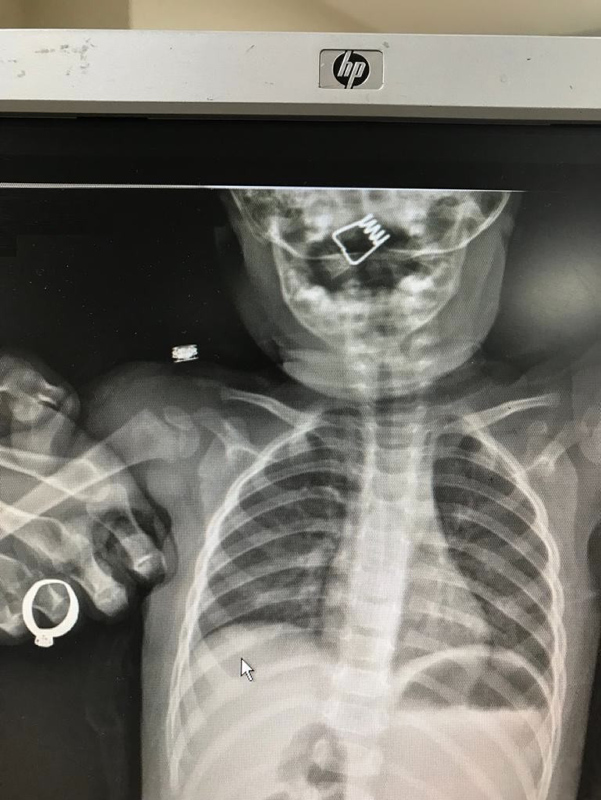

Nevşehir Devlet Hastanesi Acil Polikliniği'ne getirilen bebeği, Acil Nöbetçi doktoru Mustafa Alpaslan muayene ederek gerekli tetkikleri yaptı. Çekilen röntgen filmlerinde mandal yayının lokalizasyonu ve durumu belirlendi. Daha sonra, KBB Uzmanı Op. Dr. Ahmet Cevatzade tarafından yapılan başarılı ameliyat sonucunda bebeğin genzine saplanan mandal yayı çıkartıldı.